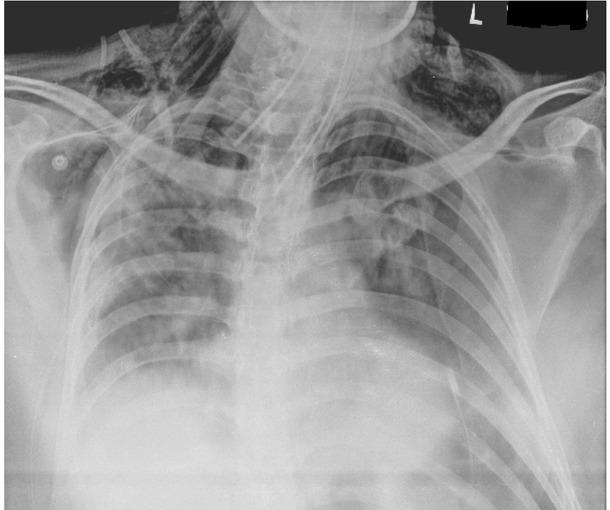

Fig. 2A